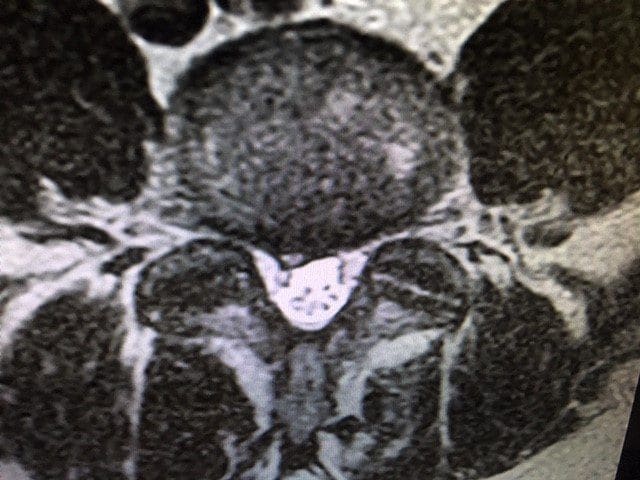

- There is a 5.7 mm wide focal protrusion type disc herniation at L4-5 which impinges on the thecal sac.

T2 Axial L4-5: Focal Disc Protrusion Type Herniation

Definition: Herniation is defined as a localized or focal displacement of disc material beyond the limits of the intervertebral disc space.3

Protrusion Type Herniation: is present if the greatest distance between the edges of the disc material presenting outside the disc space is less than the distance between the edges of the base of that disc material extending outside the disc space.3